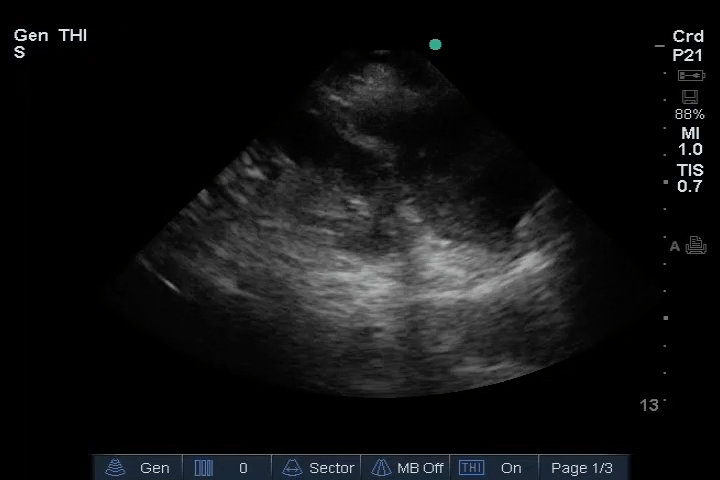

Heart: Dilated right ventricle (RV), most clearly visualized in the PSAX view. An embolus is visible in the right atrium (RA).

12_Heart_PLAX – Dilated RV, RA embolus

13_Heart_PSAX – Dilated RV